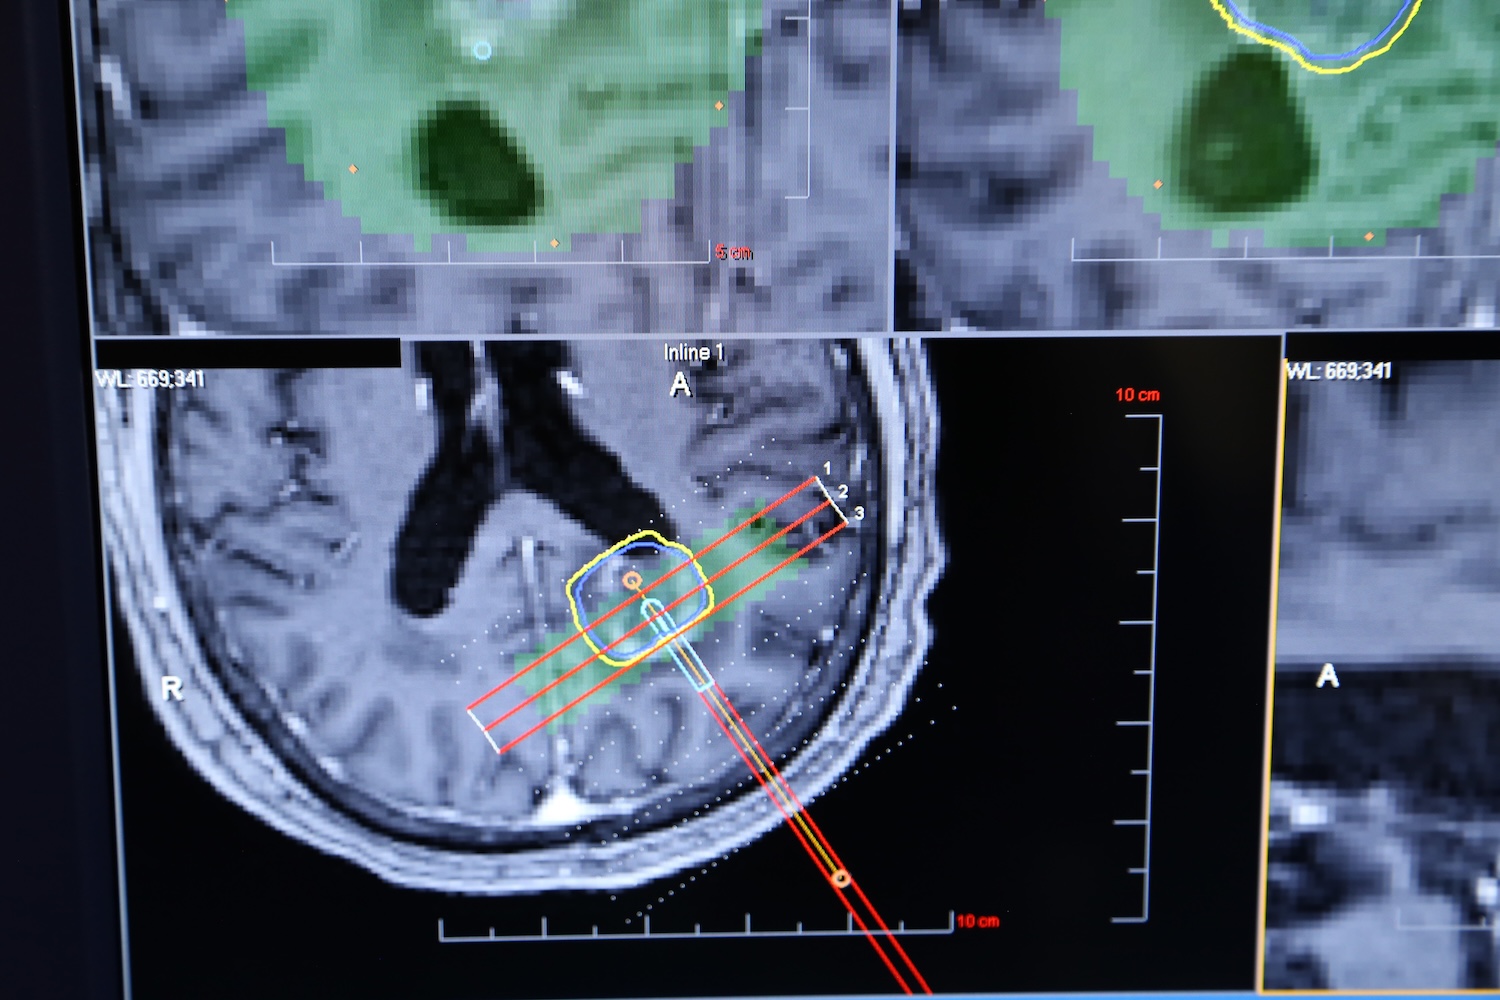

“During the ablation, surgeons monitor the temperature in real time through MRI imaging, allowing them to see exactly how the heat is affecting the tumor,” Gersey explains. “If critical structures are nearby, the system can limit or block heat from spreading into those areas. Should temperatures rise too high, the system will automatically shut down.”

Graphic of an MRI showing a brain scan during a procedure